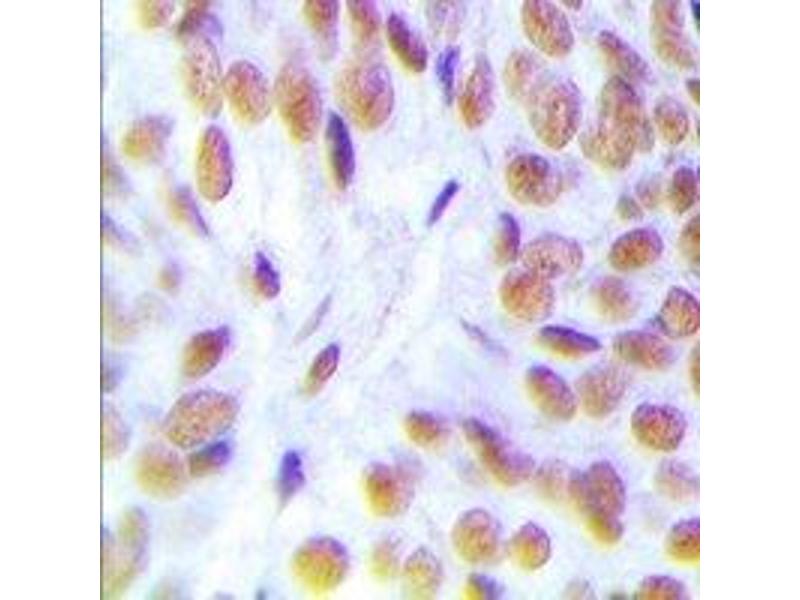

Glucocorticoid Receptor Anticorps

(Nuclear Receptor Subfamily 3, Group C, Member 1 (Glucocorticoid Receptor) (NR3C1))

Découvrez des anticorps Glucocorticoid Receptor fiables issus d’une large sélection de fabricants renommés. Notre portefeuille permet une détection précise de Glucocorticoid Receptor dans plusieurs espèces, y compris Human, Mouse, Rat, Zebrafish (Danio rerio), Cow, Rabbit, Horse, Sheep, Monkey, Pig, Guinea Pig, Chicken, Hamster, et prend en charge diverses applications de recherche telles que WB, IHC, ELISA, IF, FACS.